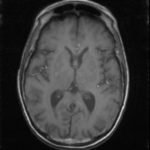

The patient had a witnessed episode of isolated left upper extremity jerking, shown in the video, during which she was completely awake and conversant. Lab results were significant for serum glucose of 1167 mg/dL, no anion gap, and negative serum/urine ketones. She had a computed tomography (CT) of the head that did not show any acute pathology, and underwent a brain magnetic resonance imaging (MRI) without any signs of stroke or other pathology, shown below.

Hyperglycemic hemichorea hemiballismus is a rare complication of hyperosmolar hyperglycemic non-ketotic syndrome (HHNS) and encompasses a range of non-patterned, involuntary movements on one side of the body.1 The pathophysiology is not fully understood, but one hypothesis suggests an increased inhibition of the subthalamic nucleus and reduction in GABA-ergic inhibition in the thalamus.2 The characteristic lesions seen on radiology include hyperdensities of the putamen, head of the caudate, and globus pallidus on CT and T1-weighted MRI contralateral to the side with symptoms, but these findings are not always seen (as in this case), nor are they specific for this disease process.3 The differential for these type of lesions also includes subacute hemorrhage, calcifications, and metal deposition.4 Most cases are benign and resolve with one to two days of normoglycemia; however, some patients can have persistent symptoms for months.2 Review of previous case reports revealed that this dyskinesia occurred more often among elderly diabetic patients but could also be an initial presentation of diabetes.5